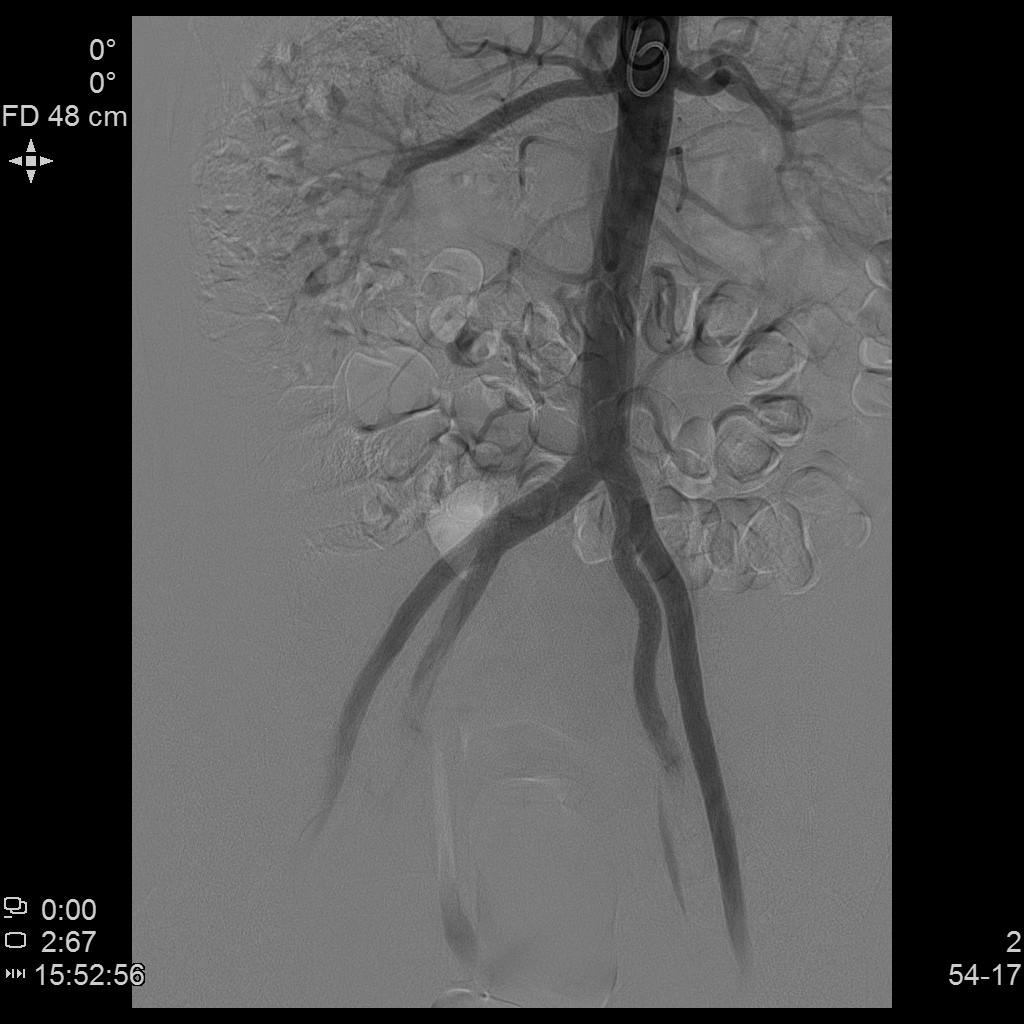

- 经桡动脉入路置入导管造影显示双侧子宫动脉明显增粗,染色丰富,子宫明显增大。

腹主动脉造影